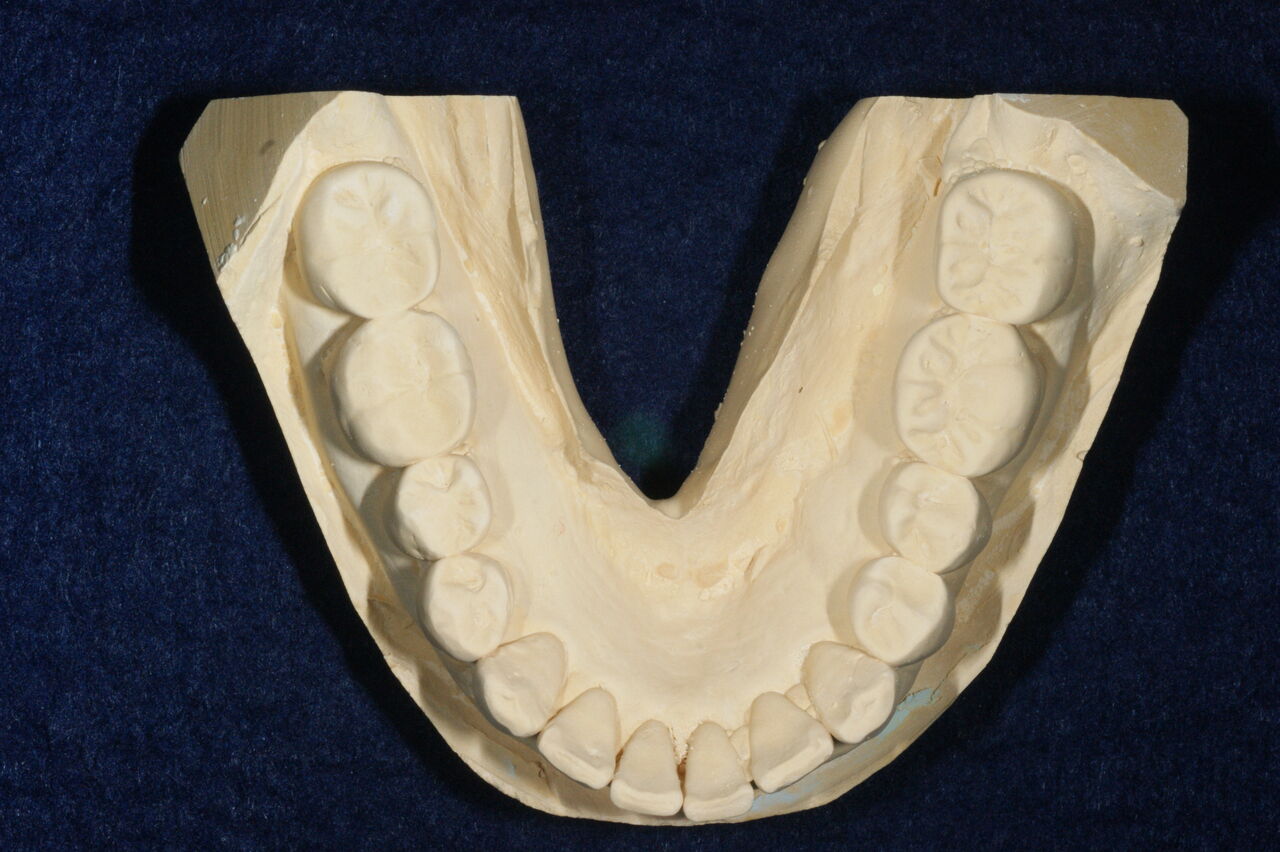

口腔内は、比較的まめに治療を受けている様子で、刷掃状態も良好、歯の健康に関する意識はかなり高い方だと思います。咬合に関して変更が要求される問題点はないと判断しました。通法にのっとり必要な齲蝕処置、根管治療、歯周病治療、不適合修復物の再製等をおこないました。問題点の解決後、健康維持のため、齲蝕および歯周病予防に関わる歯垢および歯石の抑制プログラムを施行し、今日現在14回目の定期検診で来院中です。

長期的健康維持を視野においたとき、この患者さんの問題点を挙げるとすれば、それはブラキシズムです。この11年間で、修復物の脱離や破折、歯牙歯頚部の楔状欠損および咬合面咬頭の破折等の問題が起きています。